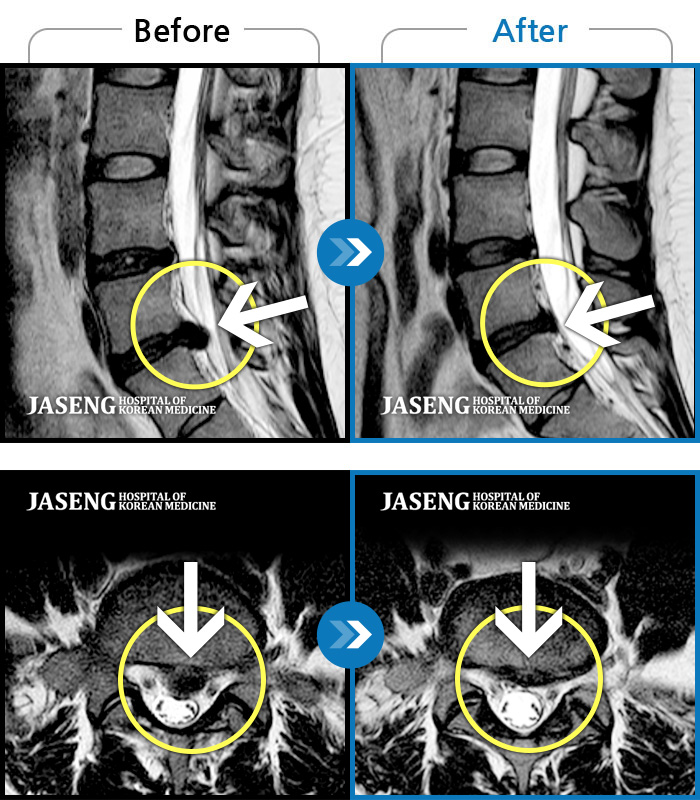

허리디스크

천안 · 김세정 원장

직업 상 무거운 물건을 많이 드는 편으로 6개월간 허리와 둔부의 통증이 지속되었으나 내원 2주 전부터 야간통증까지 동반되어 내원하였습니다.

촬영시기

2022.05.27 ~ 2024.11.02